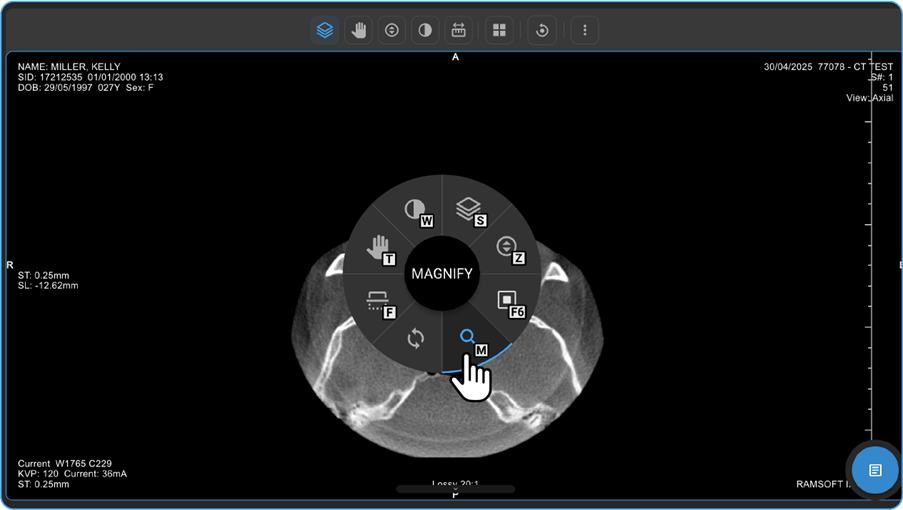

What does the Adjustment Wheel do, and how do I find it in the viewer?

The Adjustment Wheel in the OmegaAI Image Viewer offers a powerful set of tools to enhance your view, analysis, and interaction with medical images.

To open the Adjustment Wheel:

- On the home page of Blume, go to Completed Studies, open the desired study, and click View Images.

- In the Image Viewer, right-click anywhere on the image.

- The Adjustment Wheel will appear, displaying multiple image manipulation and analysis tools.

Key Features of the Adjustment Wheel

- Zoom & Magnify

- On the Blume Homepage, go to the Completed Studies, open the desired study, and click View Images.

- On the image viewer, Right-click anywhere on the study image to open the adjustment wheel.

- You can locate the looking glass icon on the lower side of the wheel. When you hover the cursor over the icon, it brightens in Blue, and you can see the name "Magnify" in the middle of the wheel.

- Select the Magnify option.

- Hold the left mouse button and move the mouse in desired directions over the image to see the magnified view of the part/region of the image.

- Alternatively, you can also locate the Up-Down Arrow inside a Circle icon, which represents the Zoom In/Out function.

- Hover your cursor over the icon to see it illuminate and display its name, "Zoom," at the centre of the wheel.

- Click on the Zoom icon.